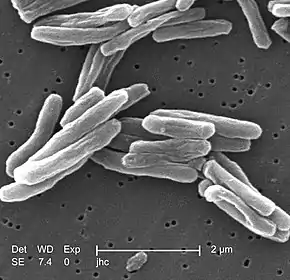

Mycobacteria

The main cause of TB is Mycobacterium tuberculosis (MTB), a small, aerobic, nonmotile bacillus.[8] The high lipid content of this pathogen accounts for many of its unique clinical characteristics.[23] It divides every 16 to 20 hours, which is an extremely slow rate compared with other bacteria, which usually divide in less than an hour.[24] Mycobacteria have an outer membrane lipid bilayer.[25] If a Gram stain is performed, MTB either stains very weakly "Gram-positive" or does not retain dye as a result of the high lipid and mycolic acid content of its cell wall.[26] MTB can withstand weak disinfectants and survive in a dry state for weeks. In nature, the bacterium can grow only within the cells of a host organism, but M. tuberculosis can be cultured in the laboratory.[27]

Using histological stains on expectorated samples from phlegm (also called sputum), scientists can identify MTB under a microscope. Since MTB retains certain stains even after being treated with acidic solution, it is classified as an acid-fast bacillus.[14][26] The most common acid-fast staining techniques are the Ziehl–Neelsen stain[28] and the Kinyoun stain, which dye acid-fast bacilli a bright red that stands out against a blue background.[29] Auramine-rhodamine staining[30] and fluorescence microscopy[31] are also used.